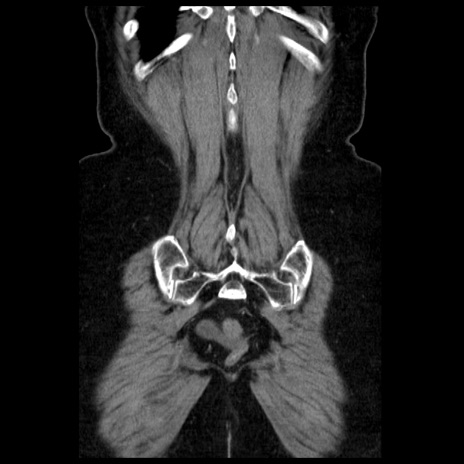

症例13(冠状断像)

【症例】70歳代女性

【主訴】腹痛、嘔吐

【現病歴】15時間程前(昨晩)より腹痛あり。今朝になっても症状の改善なく、嘔吐あり。腹痛も増悪あり、救急外来受診。

【既往歴】子宮癌全摘術後

【身体所見】意識清明、BP 121/72mmHg、P 74bpm、SpO2 100%(RA)、腹部:平坦・軟、腸雑音ほぼ聴取せず。下腹部・心窩部・臍左上に圧痛あり。反跳痛なし。

【データ】WBC 10600、CRP 0.15